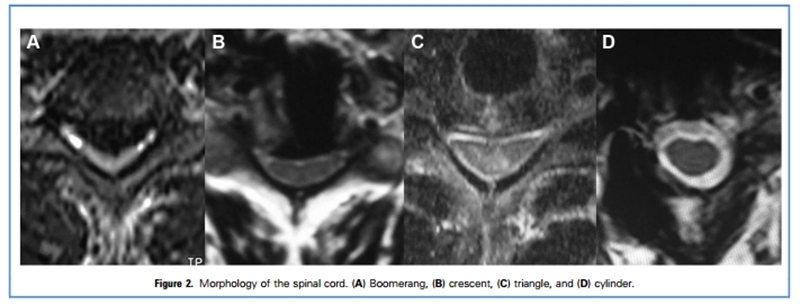

研究将脊髓横截面形态分为回旋镖形、月牙形、三角形和圆柱形。研究发现,ACAF组患者术后脊髓形态恢复明显优于ACCF组,提示ACAF可提供更好的椎管扩大效果。